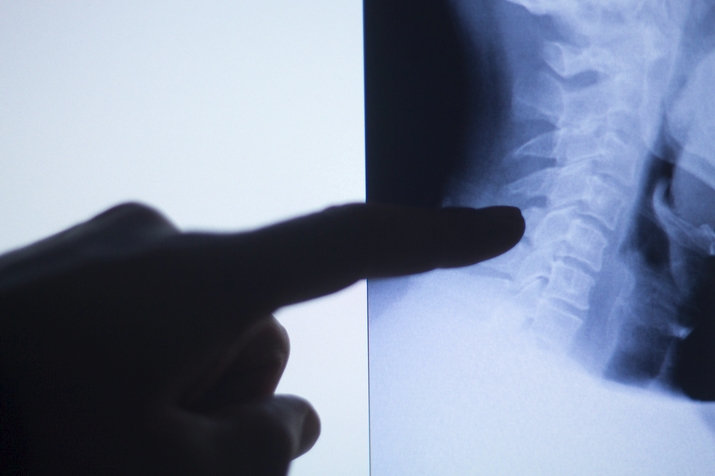

일자목과 거북목은 비슷한 듯하지만 그 원인과 진행 양상에서 차이가 있습니다. 일자목은 경추의 C자 곡선이 사라지며 직선으로 변한 상태이고, 거북목은 그보다 더 심화되어 목이 몸통보다 앞으로 빠져나온 체형까지 바뀐 경우입니다. 쉽게 말해, 일자목은 정적인 구조의 변화라면 거북목은 역동적인 자세의 변형이라고 할 수 있죠. 일자목은 비교적 초기에 발견되면 교정이 어렵지 않지만, 거북목은 어깨 말림이나 등 근육의 긴장, 허리 통증까지 이어지기 때문에 더 복잡한 교정 과정이 필요합니다.

- 일자목은 꼭 치료가 필요한가요? 증상이 가볍더라도 장기적으로 디스크나 만성 통증으로 이어질 수 있으므로 조기 대처가 필요합니다.

- 거북목은 수술로 치료하나요? 대부분은 비수술적 방법으로 개선이 가능하며, 수술은 신경 압박 등 특수한 경우에만 시행됩니다.